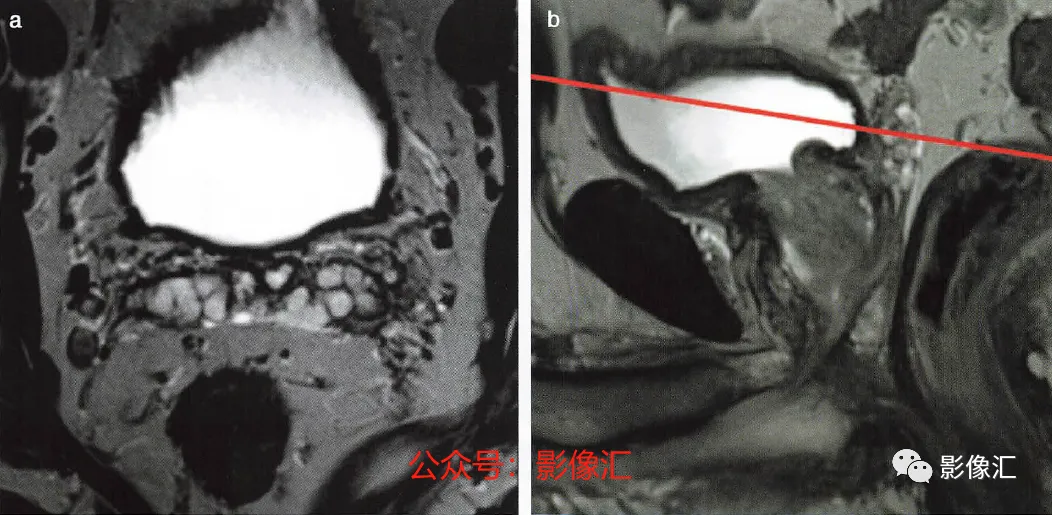

4.精囊水平的横轴面(图2.22)